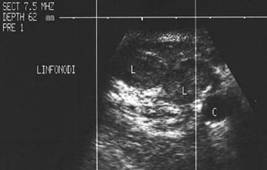

Prezenta de linfonoduli laterocervicali.

Femeie de 29 ani. Linfonodul in regiunea

laterocervicala dreapta ( 7x12x23mm, 1 cc) in neoplazie papilara a tiroidei. Structura

parenchimatoasa, neomogenea, cu margini

nete, cu absenta hilului.Examen citologic: metastaza de neoplazie papilara.